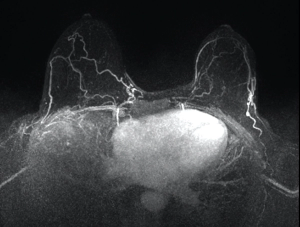

These ten images can help ob/gyns recognize the additional information GBCA administration provides in MRIs.

Gadolinium-based intravenous contrast agents (GBCA) provide additional information based on signal intensity changes after GBCA administration.